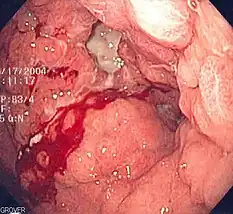

- Blood vessel rupture as a result of high blood pressure, aneurysms, peptic ulcers, or ectopic pregnancy.[8]

It is crucial to stop the internal bleeding immediately (achieve hemostasis) after identifying its cause.[4] The longer it takes to achieve hemostasis in people with traumatic causes (e.g. pelvic fracture) and non-traumatic causes (e.g. gastrointestinal bleeding, ruptured abdominal aortic aneurysm), the higher the death rate is.[4]

Unlike with external bleeding, most internal bleeding cannot be controlled by applying pressure to the site of injury.[12] Internal bleeding in the thorax and abdominal cavity (including both the intraperitoneal and retroperitoneal space) cannot be controlled with direct pressure (compression). A patient with acute internal bleeding in the thorax after trauma should be diagnosed, resuscitated, and stabilized in the Emergency Department in less than 10 minutes before undergoing surgery to reduce the risk of death from internal bleeding.[4] A patient with acute internal bleeding in the abdomen or pelvis after trauma may require use of a REBOA device to slow the bleeding.[4] The REBOA has also been used for non-traumatic causes of internal bleeding, including bleeding during childbirth and gastrointestinal bleeding.[4]